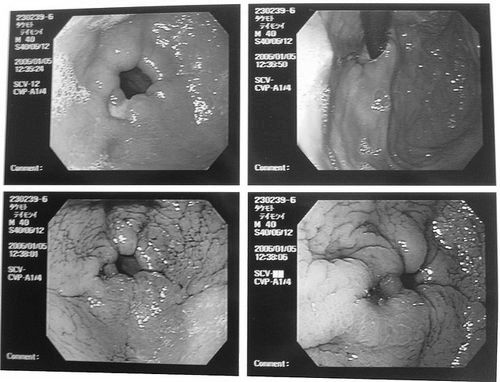

Загострення виразки шлунка на ФГДС

Зміни при загостренні виразки шлунка та 12-палої кишки